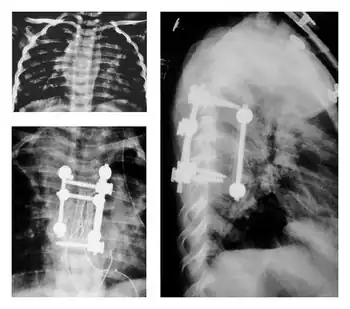

Pediatric surgical interventions

2 year old child surgery-preoperative and postoperative plain roentgenograms

In children with Pott's disease, earlier surgical intervention is often recommended to reduce their increased risk for kyphotic deformity.[1]

This increased risk for deformity is attributed to both the anatomy and biomechanics of children and their developmental stage of life.[1][31]

Due to the proportions of their bodies , limited muscular development, and increased flexibility, gravity can lead to greater deformation and presentation of kyphosis.[31]

After onset of the disease, growth plates in the spine may be destroyed and vertebral bodies suppressed due to kyphosis.[31]

These variable complications would then further deformation, leading to uncontrolled and/or suppressed growth.[31]